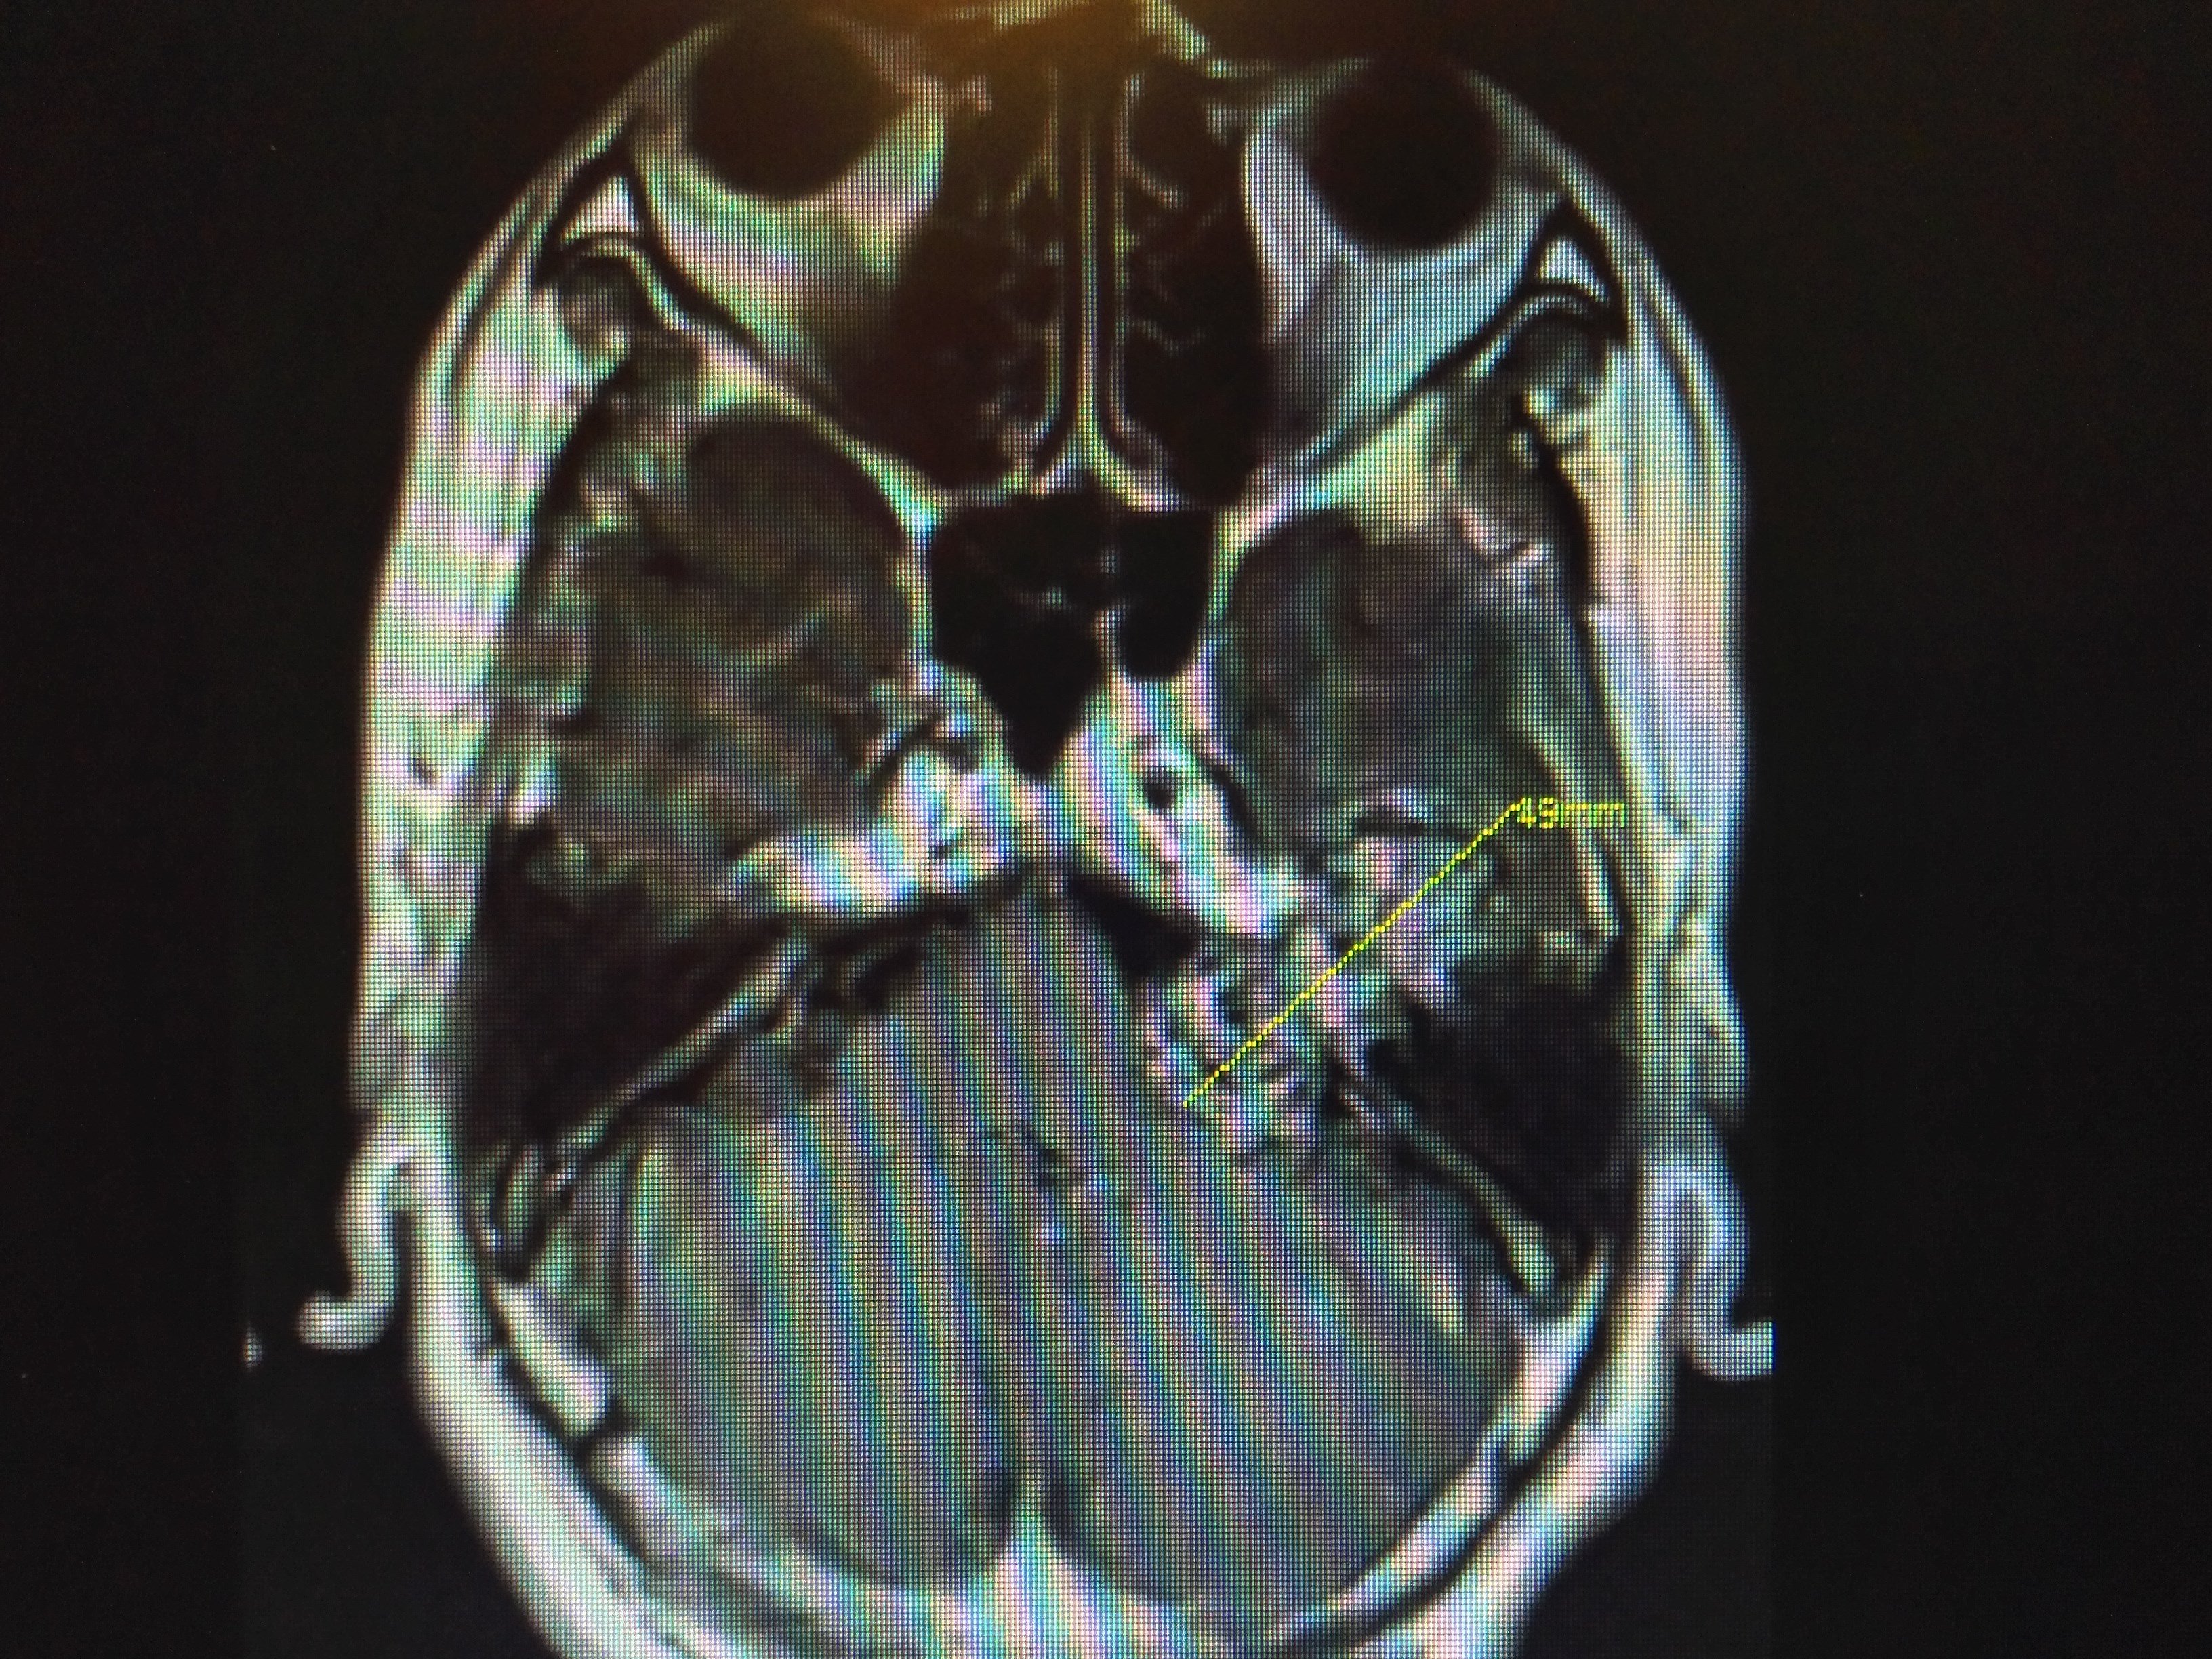

一组实质性听神经瘤全切,面神经全部解剖保留 - 好大夫在线

图片尺寸3264x2448